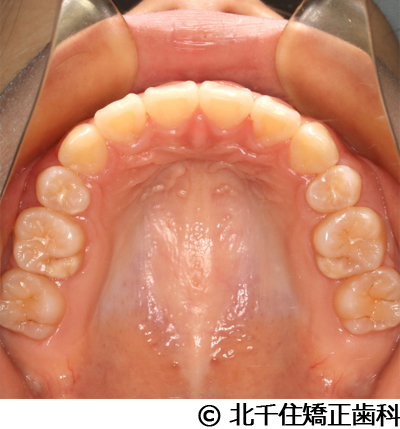

【症例3】叢生

- 治療前

- 治療後

- 治療名

- 叢生

- 費用

- 1,125,000円(税込)

- 期間

- 2年1ヵ月

- 治療回数

- 26回

- 通院頻度

- 1ヵ月ごと

- 年齢・性別

- 19歳3ヵ月・女性(初診時)

治療内容

-

患者様の症状

主訴:デコボコ、口元の突出

治療方法

上下顎第一小臼歯4本を抜歯してワイヤー矯正(セラミックブラケット)。

治療結果

叢生に対し抜歯を併用した矯正治療により、歯列および咬合関係の調整を行った症例である。治療後は保定装置を使用し、歯列および咬合の安定維持を目的として定期的な経過観察を行っている。

※治療結果は個人差があります。

治療を行う上での注意点(リスク・副作用)

歯磨き不良に伴うカリエスや歯周病、歯根吸収など。